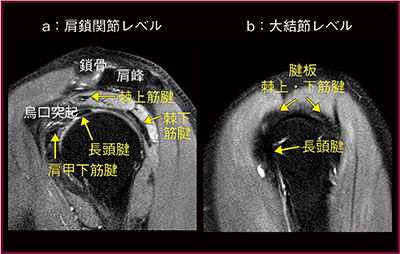

画像に何か見えたら,隣のスライス,隣のスライスと“連続して追いかける”ことが重要である。1つのスライスでわからなくても,スライスを連続して追いかけることで同定することができる。筋肉には起始部があり,関節を越え別の骨に停止する。例えば,棘上筋は肩甲骨棘上窩が,棘下筋は肩甲骨棘下窩が起始部であるが,共に大結節が停止部となる。矢状断の肩鎖関節レベルのスライスでは上に棘上筋,下に棘下筋が分かれて見えるが(図3a),大結節側にスライスを追っていくと,徐々に近づいて停止部では一塊にくっついている(図3b)。そして,この部分が最も断裂が起こりやすい。読影では,正常構造を理解した上でスライスを連続して追いかけて,さらに各撮像断面,各種シーケンスで観察することが大切である。

図3 脂肪抑制T2強調画像,矢状断